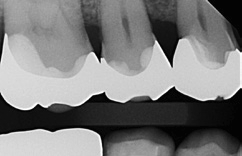

Bei dem 57-jährigen Patienten imponierte in der Routine-Bissflügelaufnahme eine Sekundärkaries an dem mit einem Gold-inlay versorgten Zahn 14 (Abb. 1). Der vitale und symptomfreie Zahn zeigte lediglich radiologisch (Abb. 2) einen Randdefekt distal sowie den Verdacht auf Karies unter dem Befestigungs- bzw. Unterfüllungszement. Nach Entfernung des Goldinlays ergab sich der Verdacht auf eine Pulpaeröffnung (Abb. 3). Klinisch war keine Blutung feststellbar, was allerdings durch die Lokalanästhesie kaschiert sein konnte. Aufgrund der Symptomlosigkeit des Zahnes und fehlender Anzeichen einer Pulpitis (fehlende Blutung) sowie einer Nekrose (erhaltene Vitalität) fiel die Entscheidung zugunsten einer Vitalerhaltung unter Beibehaltung eines engmaschigen Recalls mit Vitalitätsproben. Die Überkappung der Eröffnungsstellen erfolgte als Alternative zu Calciumhydroxid [8] mit einem Portlandzement enthaltenden Flowkomposit mit hohem pH-Wert [7,51] (TheraCal LC, Bisco, Abb. 4). Obwohl dieses Produkt hinsichtlich seiner Effektivität und Zelltoxizität nicht an ProRoot MTA (Dentsply Sirona) und Biodentine (Septodont) [42] herankommt [5,11], ist es hinsichtlich seiner Praktikabilität und der Möglichkeit des sofortigen, zügigen Weiterarbeitens konkurrenzlos. Ein vergleichbares Produkt gibt es z.B. bei Ultradent (Ultra- Blend Plus).